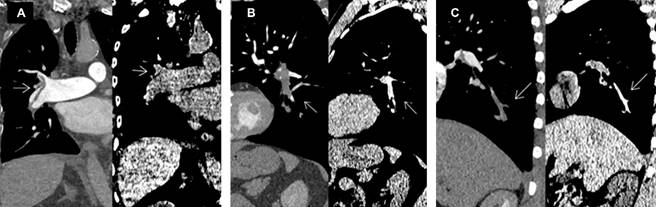

Se determinó asociación entre la trombosis pulmonar y la arteria segmentaria afectada, con resultados estadísticos significativos (p = 0.03), y OR de 4.33, IC95% 1.60-11.69; en consecuencia, el compromiso de la arteria segmentaria se considera un factor de riesgo para TEP. De la misma manera se evidenció la asociación entre la presencia del signo de vaso hiperdenso con el tipo de trombosis pulmonar (parcial o completa), con valor de p = 0.001, altamente significativo, y OR de 6, con IC95% 1.003-35.905), debido a lo cual, la presencia del signo de vaso hiperdenso, evidenciado mediante TC simple de tórax, es un factor de riesgo para desarrollar TEP (Tabla 1 y Figura 3).

Figura 3: A) Caso negativo. B y C) Tromboembolismo pulmonar con signo de vaso hiperdenso en vista coronal.